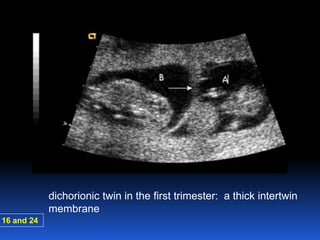

dichorionic twin in the first trimester: a thick intertwin

membrane

16 and 24